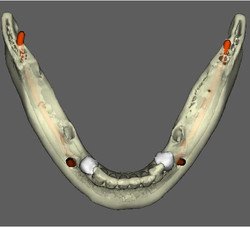

Caso 5: Dente retido

Dente 47 e 48 retidos, em posição mésio horizontal, sobrepostos com raízes superpostas ao canal mandibular. Ao exame tomográfico identifica-se o canal passando rechaçado entre os ápices do 48 e a cortical vestibular e passando entre as duas raízes mesiais do dente 47.

CIRURGIA GUIADA

O Dental Slice é uma ferramenta de planejamento implantodôntico pré-operatório, desenhado para oferecer auxílio cirúrgico-protético com alto nível de precisão e aumentar a margem de segurança no tratamento.

O programa é acessível a qualquer cirurgião dentista e permite que o planejamento seja realizado pela própria equipe que vai realizar a cirurgia. As imagens também podem ser segmentadas, oferecendo melhor visualização de detalhes, como por exemplo do seio maxilar, canal da mandíbula ou de lesões.